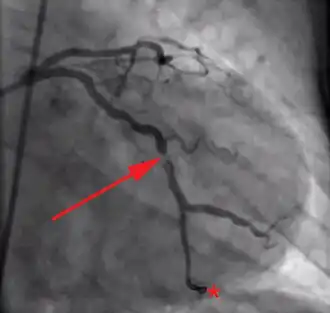

Acute coronary syndromes are caused by sudden and critical reduction of blood flow in one of the coronary arteries, the vessels that supply oxygenated blood to the myocardium (heart muscle), typically by a blood clot. The principal symptom is typically chest pain, known as angina pectoris; people who present with angina must prompt evaluation for possible acute coronary syndrome.[2]

Acute coronary syndromes are classified to two major categories, according to the patient's electrocardiogram, and specifically the presence or absence of persistent (>20 min) ST segment elevation (or left bundle branch block).[2] Patients with acute coronary syndrome and ST elevation are said to have ST-elevation myocardial infarction (STEMI) and they tend to have one of their coronary arteries totally blocked.[3] Damage is reversible for approximately 20[4]-30[5] minutes after complete obstruction of blood flow; thereafter myocardial cell death ensues and progresses as time passes. Therefore, complete and sustained restoration of blood flow must be as prompt as possible to ensure maximum salvage of functional myocardium, a principle expressed in the maxim "time is muscle".[6] This is achieved with reperfusion therapy, which is based on invasive reopening of the affected coronary artery with primary percutaneous coronary intervention, or non-invasive breaking up of the responsible blood clot with a thrombolytic drug.[7]

Patients without ST segment elevation are said to have non-ST-elevation acute coronary syndrome and tend not to have full occlusion of a coronary artery. If there is evidence of myocardial cell death (especially elevated cardiac biomarkers) they are considered to have a non-ST-elevation myocardial infarction (NSTEMI); otherwise they are classified with unstable angina.[8] Their management is based on the estimation of their risk for adverse events. Patients at low risk can be adequately treated with medical therapy, in many ways similar to the one used for STEMI (but excluding thrombolytics). Those at moderate to high risk benefit from an early invasive strategy, which includes coronary angiography and, if necessary, revascularization with percutaneous coronary intervention or coronary artery bypass surgery.[9]

The concept of reperfusion has become so central to the modern treatment of acute myocardial infarction, that we are said to be in the reperfusion era.[53][54] Patients who present with suspected acute myocardial infarction and ST segment elevation (STEMI) or new bundle branch block on the 12 lead ECG are presumed to have an occlusive thrombosis in an epicardial coronary artery. They are therefore candidates for immediate reperfusion, either with thrombolytic therapy, percutaneous coronary intervention (PCI) or when these therapies are unsuccessful, bypass surgery.

Individuals without ST segment elevation are presumed to be experiencing either unstable angina (UA) or non-ST segment elevation myocardial infarction (NSTEMI). They receive many of the same initial therapies and are often stabilized with antiplatelet drugs and anticoagulated. If their condition remains (hemodynamically) stable, they can be offered either late coronary angiography with subsequent restoration of blood flow (revascularization), or non-invasive stress testing to determine if there is significant ischemia that would benefit from revascularization. If hemodynamic instability develops in individuals with NSTEMIs, they may undergo urgent coronary angiography and subsequent revascularization. The use of thrombolytic agents is contraindicated in this patient subset, however.[55]

The basis for this distinction in treatment regimens is that ST segment elevations on an ECG are typically due to complete occlusion of a coronary artery. On the other hand, in NSTEMIs there is typically a sudden narrowing of a coronary artery with preserved (but diminished) flow to the distal myocardium. Anticoagulation and antiplatelet agents are given to prevent the narrowed artery from occluding.